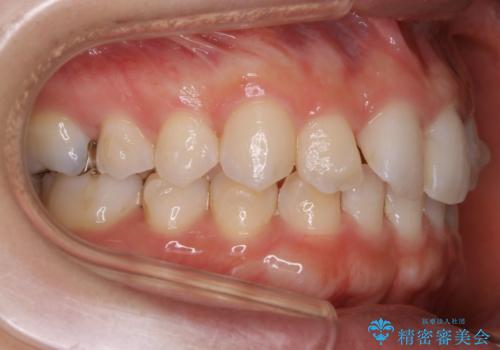

生まれつき下の前歯が1本少なく、その分のスペースを上の前歯がガタつくことで埋めているという状況でした。

上下それぞれのガタつきをとっていく過程で、歯1本分のスペースの差を、上顎の前歯のIPRで調整して並べる方法をご提案させていただきました。

稀に、乳歯が抜けてもその後に永久歯が生えてこないことがあります。生まれつき歯の元となる「歯胚」というものが欠如していることが原因で本数が少なくなることを「先天欠如」といいます。

こういったケースの治療では欠損している歯の本数分反対の顎の歯(上顎に欠損がある場合は下顎の歯)を抜歯してスペースの調整をする場合や、欠損歯の幅分のIPRを反対の顎の歯に設定することでスペースのコントロールをするという方法、欠損している歯の分のスペースを残して矯正を終了し最後にブリッジ治療やインプラントで歯の本数を増やすという方法があり、状況や患者さんの希望により選択をしていきます。